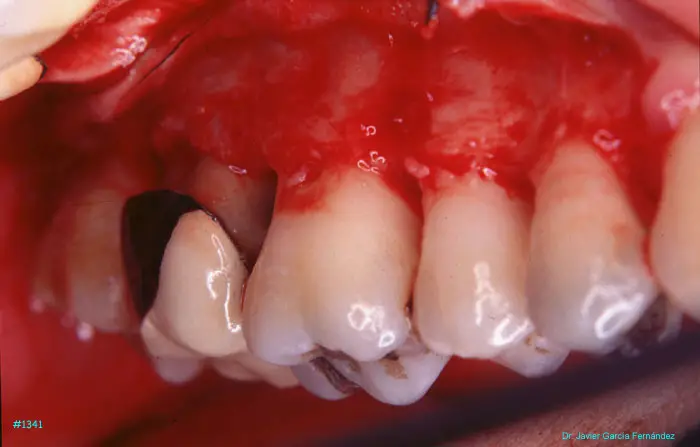

Atlas of Surgical Techniques in Periodontics. Chapter III. Atlas de Técnicas Quirúrgicas en Periodoncia